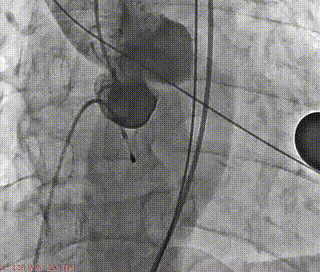

23mm球囊后扩

最终造影评估

本次手术植入瓣膜定位准确,操作简便,症状即刻改善。术后超声显示瓣口未见明显反流,微量瓣周漏,主动脉瓣前向血流加速Vmax=1.9m/s,有效开口面积2.9cm²,PGmean=8mmHg。患者生命体征稳定,手术室当场清醒,手术圆满成功。术后复查超声恢复良好,3天后出院。